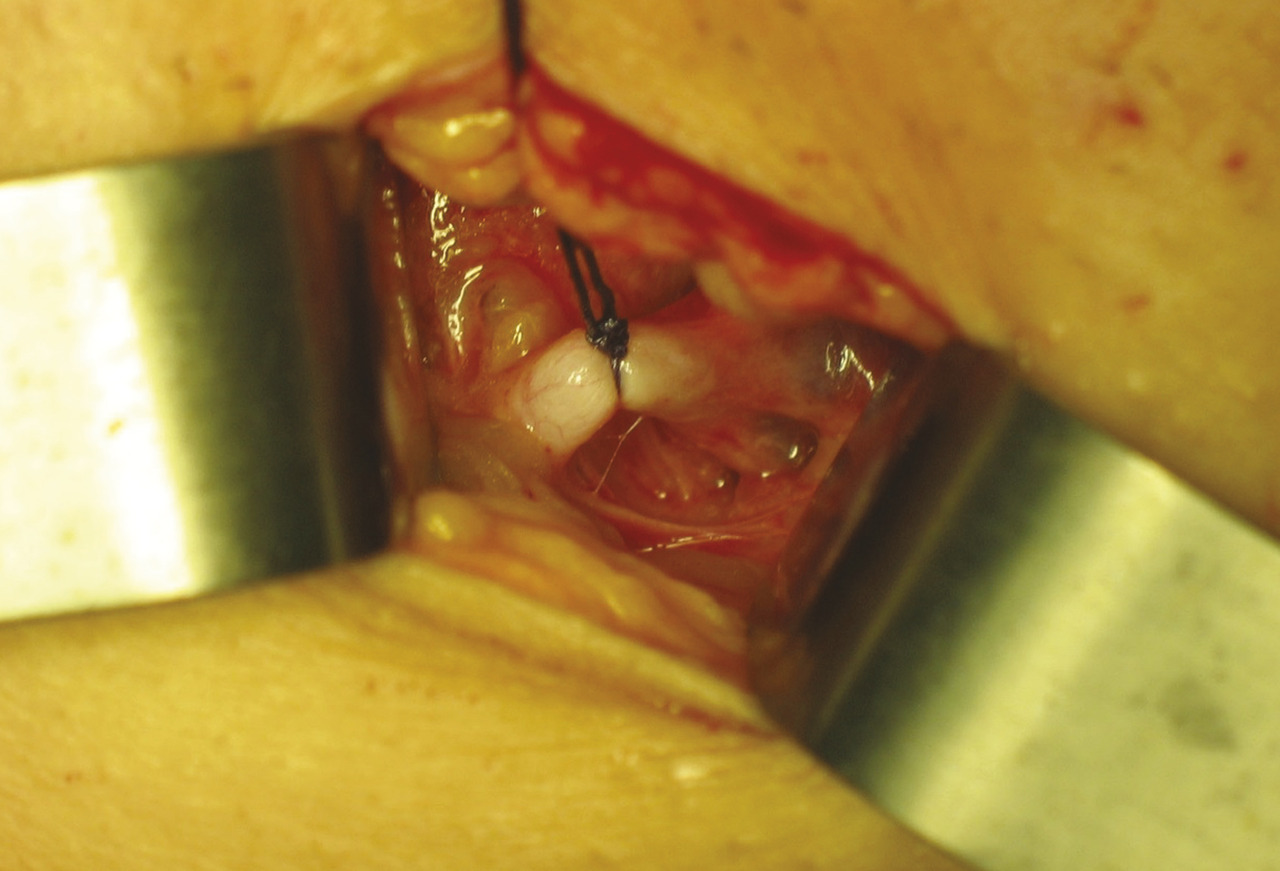

La crossectomie (réalisée au ras de la veine fémorale) est remplacée par une ligature sous les branches de la jonction saphéno-fémorale afin de diminuer les récidives par néovascularisation inguinale (fig. 1 ).4

La crossectomie (réalisée au ras de la veine fémorale) est remplacée par une ligature sous les branches de la jonction saphéno-fémorale afin de diminuer les récidives par néovascularisation inguinale (